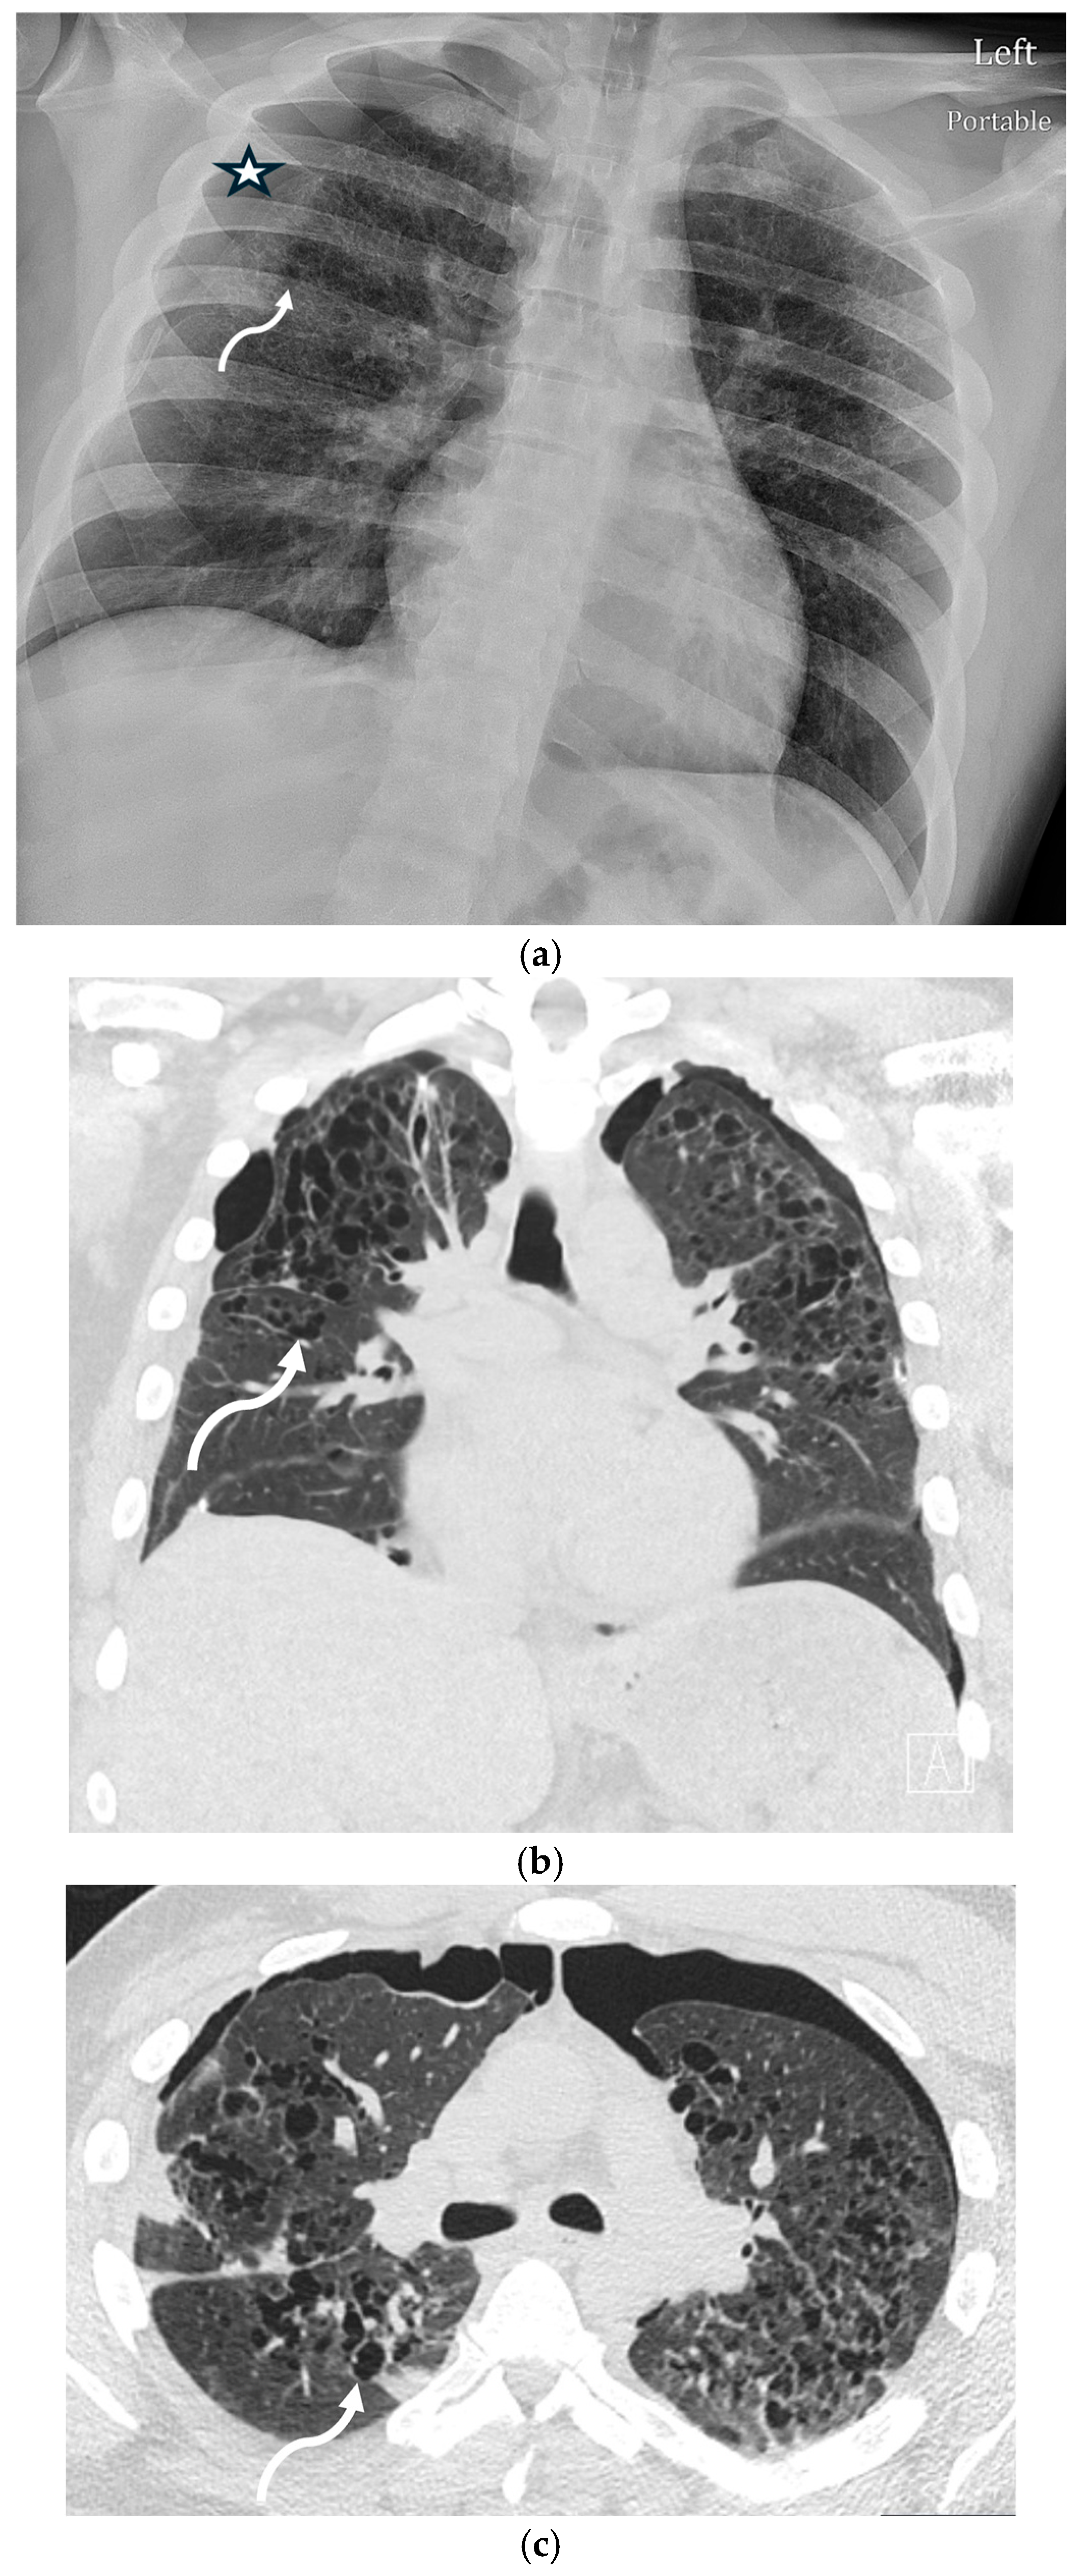

5.2.2. Cystic Fibrosis (CF)

5.2.3. Asthma